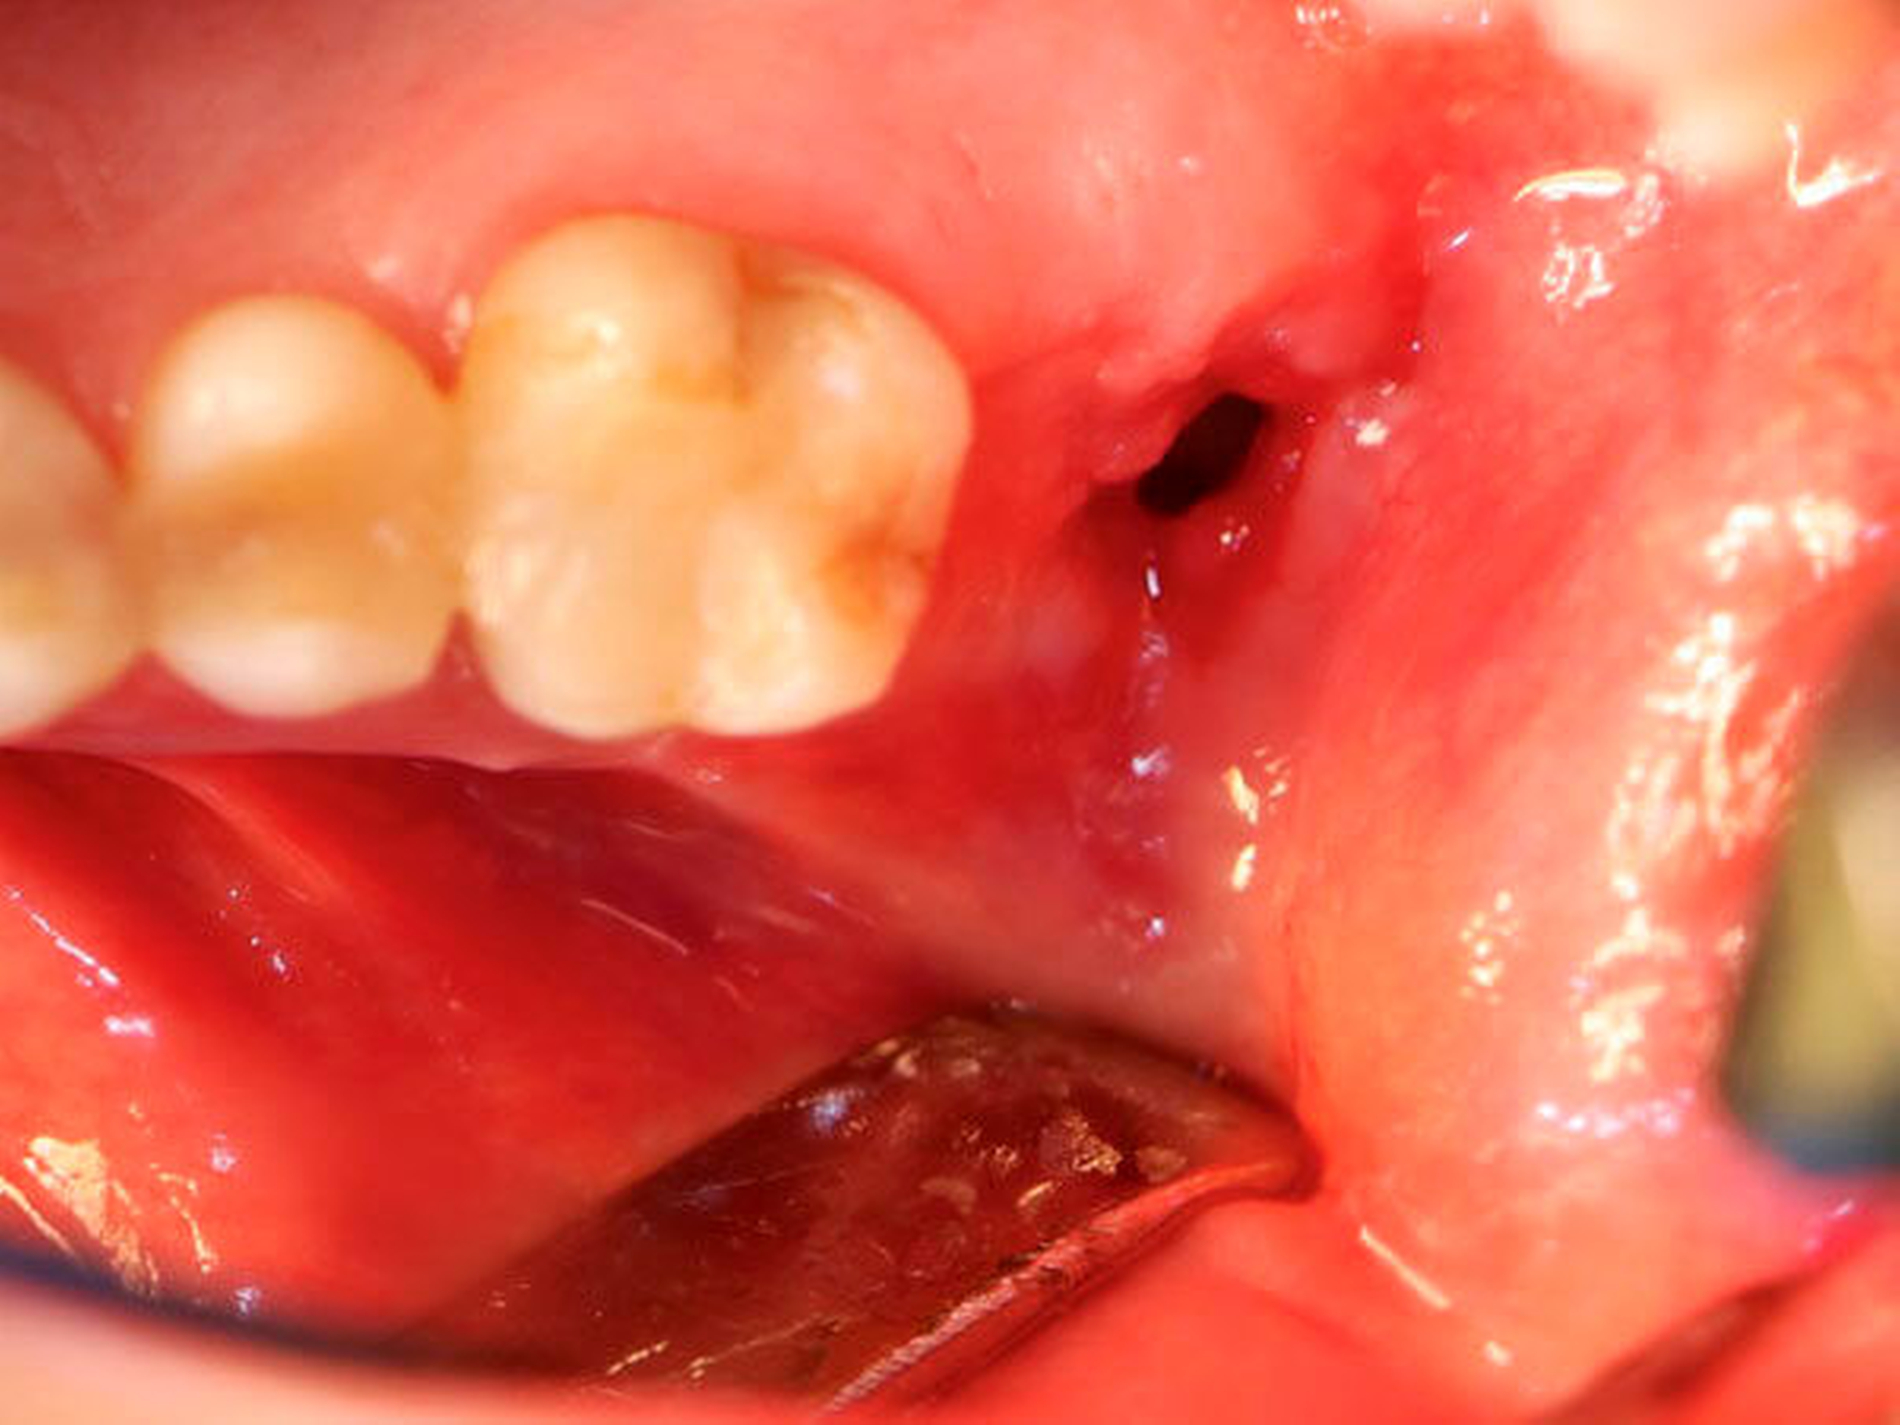

Die Allgemein- und Familienanamnese der Patientin war bis auf eine medikamentös eingestellte Hypothyreose unauffällig. Extraoral bestand kein auffälliger Befund, insbesondere keine Druckdolenz oder Nervdefizit über der Kieferhöhle links. In Regio 27 zeigte sich eine Mund-Antrum-Verbindung nach frustranem Deckungsversuch, aus der sich seröse Flüssigkeit entleerte (Abbildung 2). Der Zahn 26 reagierte negativ auf Perkussion und war avital. Nach sorgfältiger Aufklärung erfolgte die Resektion des Befunds in Intubationsnarkose. Folgend auf die Extraktion des Zahnes 26 (Abbildung 3) wurde eine Kastenresektion der linken Maxilla von distal des Zahnes 25 bis in den Tuberbereich bei makroskopischem Einhalten eines Sicherheitsabstands von 0,5 cm durchgeführt. Das narbig anmutende Gewebe in der Kieferhöhle wurde ausgeschält und en bloc mit dem Oberkieferresektat entfernt (Abbildung 4). Der Knochen wurde hier belassen, da er klinisch und radiologisch nicht infiltriert war.